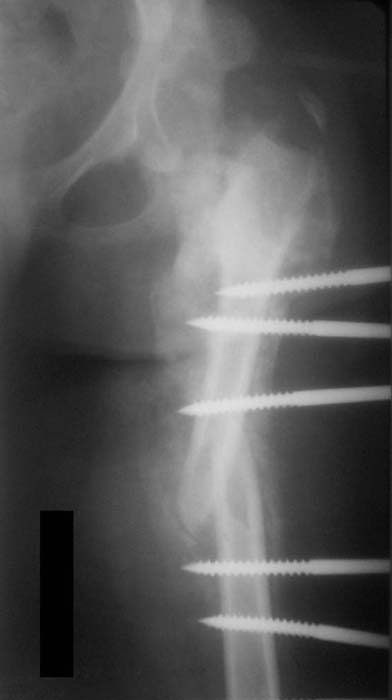

Такая мысль тоже приходила. Не решились, так как:1.Выраженный остеопороз костей таза и бедра, больная тучная - высок риск того, что стержни не выдержат. 2.Сейчас больная передвигается в инвалидном кресле - хоть какая-никакая, а динамизация. Если лишить её этой возможности - застойная пневмония со всеми вытекающими...